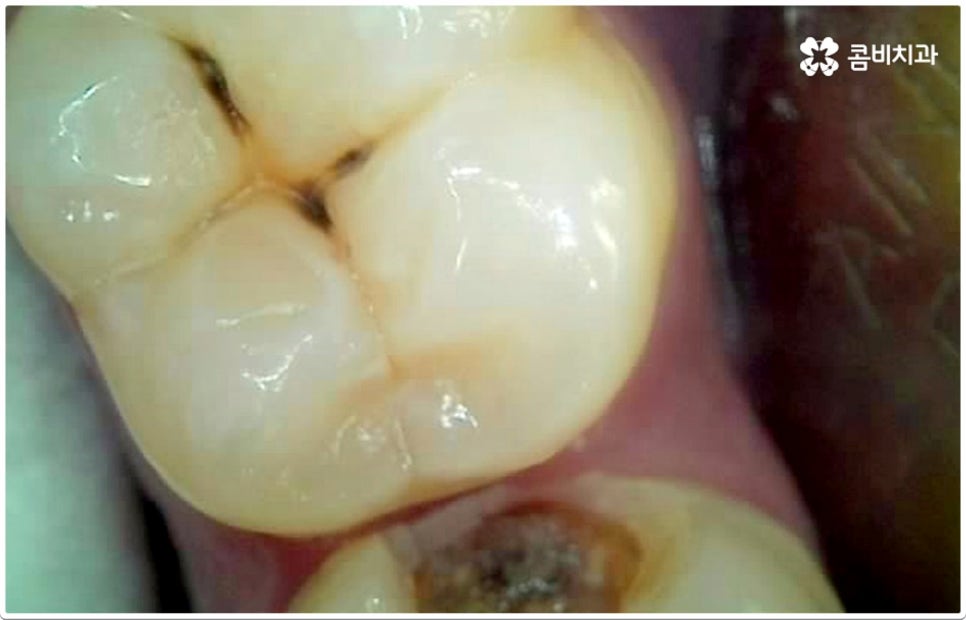

충치의 원인이 되는 세균이 급격하게 증식하게 되는 온상인 치석은 치아와 치아 사이, 또는 치아와 잇몸 사이에 플라그와 음식물 찌꺼기가 엉겨붙어 딱딱하게 굳은 것이라서 칫솔질로 제거되지 않기 때문에 주기적인 스케일링 치료를 통해 물리적으로 떼어낼 필요가 있어요. 또한 초기 충치 또는 치아사이충치 같은 경우 환자분들의 입장에서 바로 발견하는 것이 어려울 수 있기 때문에 혹시 자신이 모르는 사이에 충치가 진행되고 있지는 않은지 꼼꼼하게 살펴보고 빠르게 대처할 수 있도록 하기 위해 1년에 한 번 또는 두 번 정도 치과에 내원하셔서 정밀 검진을 받으시길 권유드리고 있습니다.

게다가 치아사이충치 는 두 치아의 인접면에 발생하여 한꺼번에 두 치아에 손상을 주기 때문에 보다 빠른 대처가 필요한데도 불구하고 말씀드린 것처럼 발견하기도 쉽지 않을 뿐더러 음식을 저작하는 치아의 교합면 (위아래 맞물리는 면) 에 생기는 충치가 아니기 때문에 수직으로 우식 부분까지 파고 내려가는 치과 충치 치료 기구들의 특성상 접근하기가 용이하지 않아 까다로운 진료에 속한다고 할 수 있어요. 특히 환자분들의 치아사이충치 발병 상황에 따라 치료 과정에서 부득이하게 삭제해야 하는 치아량이 생각보다 많아지는 케이스가 있을 수 있으므로 이에 대해 잘 알아두실 필요가 있습니다.